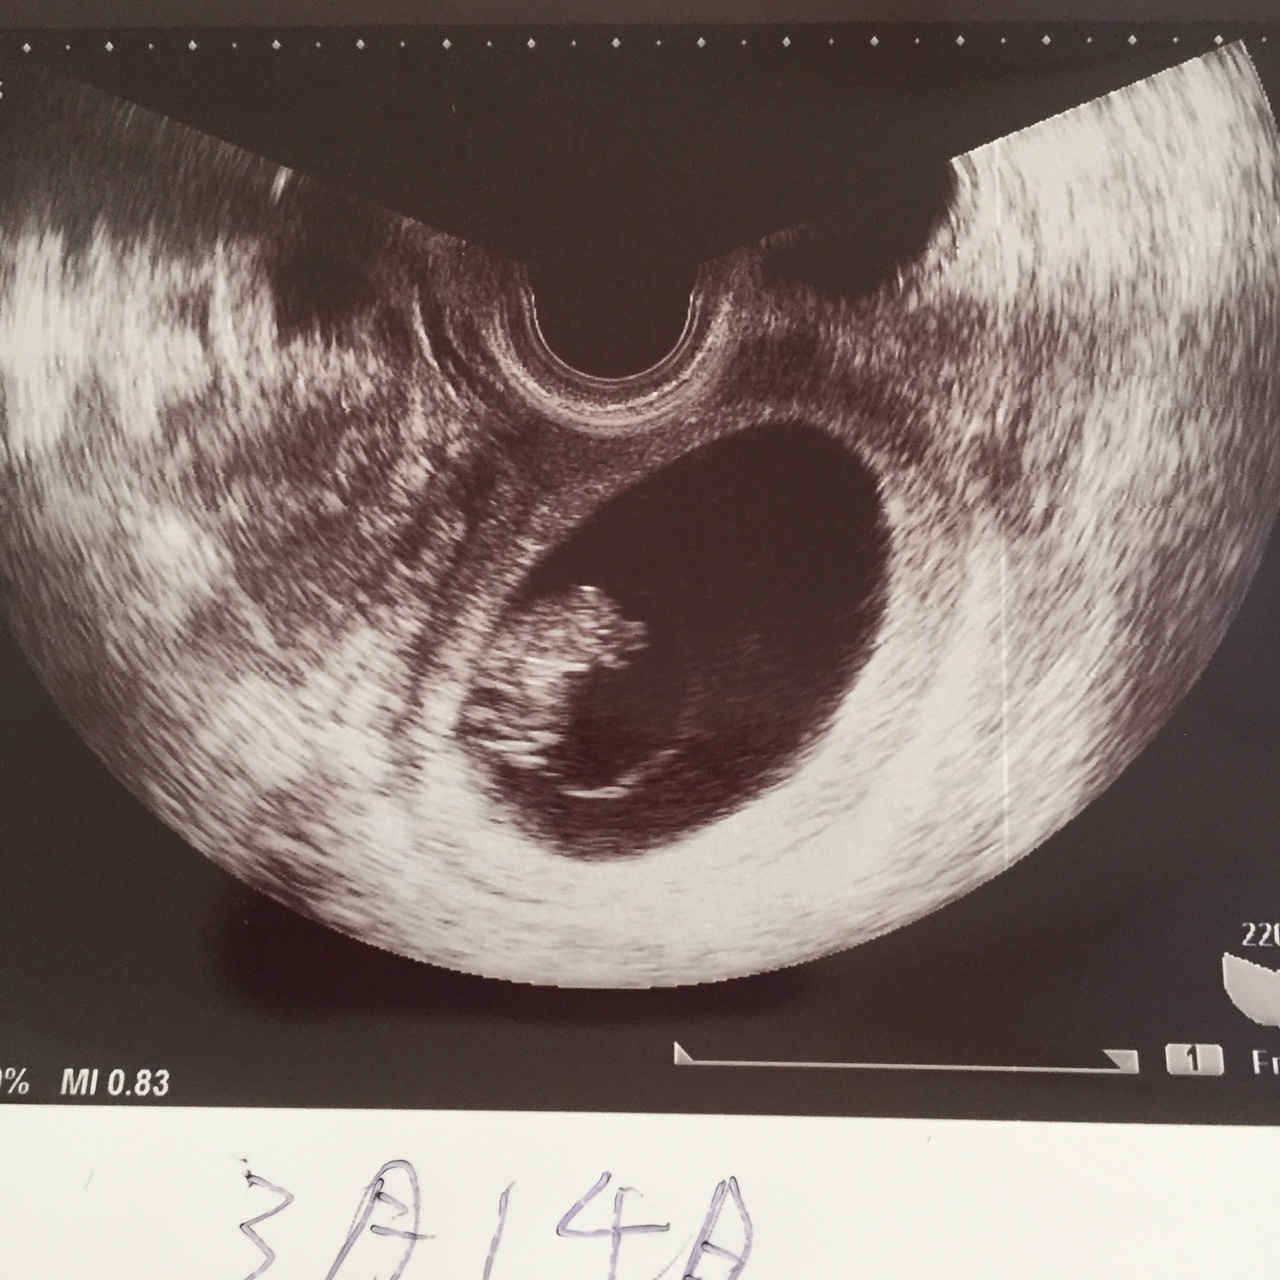

内診の結果、我が子はとっても大きくなっておりました!ヽ(=´▽`=)ノ

先生「これ、見えます?これが頭でこれが足、ここが心臓です」

私「大きくなってる!横向いてる!かわいい!!」

我が子のサイズは2センチ。ということで予定日も決まりました。

来年の3月14日の予定です。

しかし他の方のエコー写真と比べると、胎嚢が胎児に比べて大きくないだろうか…

先生には何も言われなかったので問題ないとは思いますが(;´∀`)